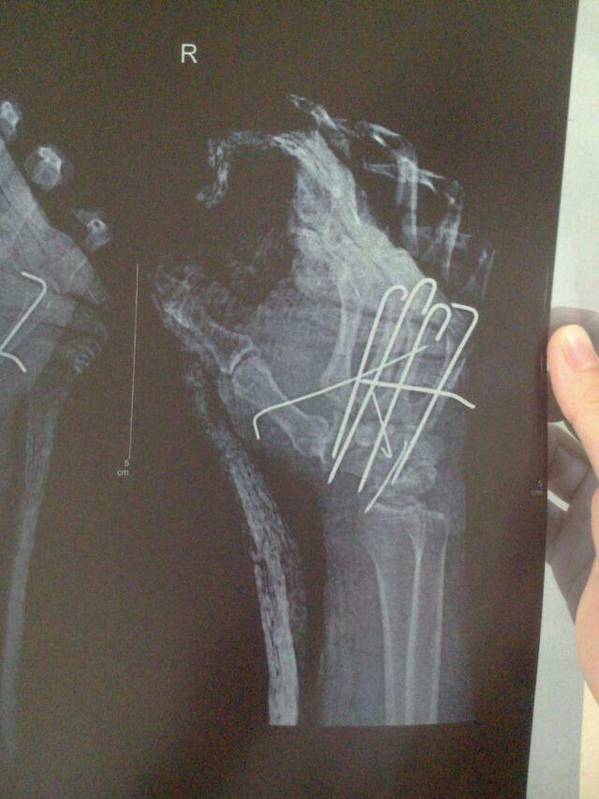

[修复重建] 右手绞榨伤

手被机器绞伤,伤后6小时入院,入院查环指无血运。术中发现桡侧腕长伸肌腱、示、中、环、小指伸肌腱腱性组织均从前臂内肌肉处撕脱,桡侧腕短伸肌腱止点撕脱,附着的腕骨脱出,第一、二、三腕掌关节不稳、脱位。望各位老师指教复位后正确固定的方法,后天复查X线后再上传。如果我固定错了就不发图了,还有肌腱怎样处理合理。如图:

今天复查术后X线结果,如有不对之处望各位老师指证

腕骨横向克氏针固定?